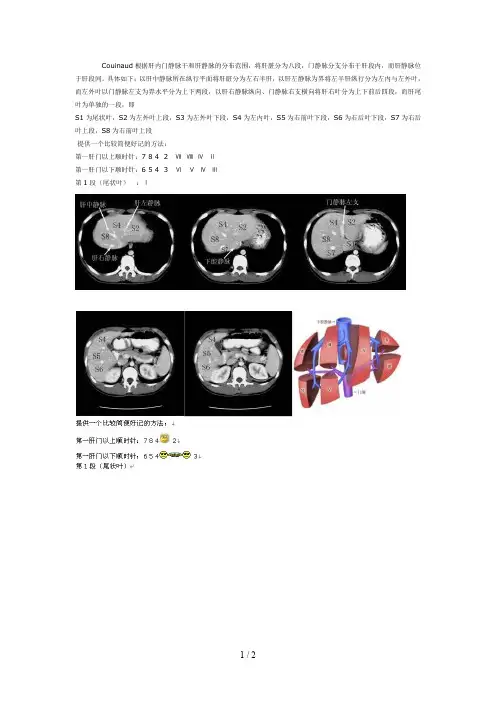

Couinaud根据肝内门静脉干和肝静脉的分布范围,将肝脏分为八段,门静脉分支分布于肝段内,而肝静脉位于肝段间。

具体如下:以肝中静脉所在纵行平面将肝脏分为左右半肝,以肝左静脉为界将左半肝纵行分为左内与左外叶,而左外叶以门静脉左支为界水平分为上下两段,以肝右静脉纵向、门静脉右支横向将肝右叶分为上下前后四段,而肝尾叶为单独的一段,即

S1为尾状叶,S2为左外叶上段,S3为左外叶下段,S4为左内叶,S5为右前叶下段,S6为右后叶下段,S7为右后叶上段,S8为右前叶上段

提供一个比较简便好记的方法:

第一肝门以上顺时针:7 8 4 2 ⅦⅧⅣⅡ

第一肝门以下顺时针:6 5 4 3 ⅥⅤⅣⅢ

第1段(尾状叶):Ⅰ